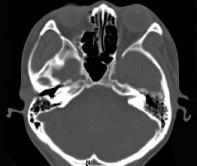

问题 女,25岁,因眼部外伤来院就诊,CT如图所示,最可能诊断是 ( )

选项 A、右眼眶内外侧壁骨折伴筛窦积血 B、蝶骨骨折伴筛窦积血 C、右眼眶内侧壁骨折伴筛窦积血 D、右眼眶外侧壁骨折伴筛窦积血 E、右侧颧弓骨折伴筛窦积血

答案 A